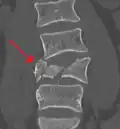

A burst fracture of L4 as seen on plane X ray -